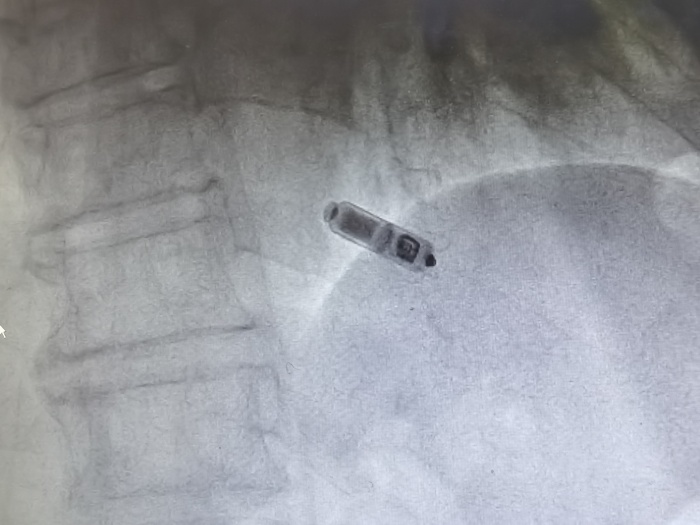

(圖示為植入心臟內(nèi)的Micra? AV無導(dǎo)線起搏器)

金奇志主任醫(yī)師告知:“無導(dǎo)線起搏器是集脈沖發(fā)生器與電極導(dǎo)線于一體的新型起搏器,無需靜脈植入心內(nèi)膜導(dǎo)線,通過以“微縮膠囊”的形式植入患者的心腔內(nèi)。無導(dǎo)線起搏器植入簡(jiǎn)單、美觀,無囊袋及導(dǎo)線植入相關(guān)并發(fā)癥,不影響肢體活動(dòng),可以明顯提高患者的自信心和治療體驗(yàn),安全性與穩(wěn)定性也比較好。”